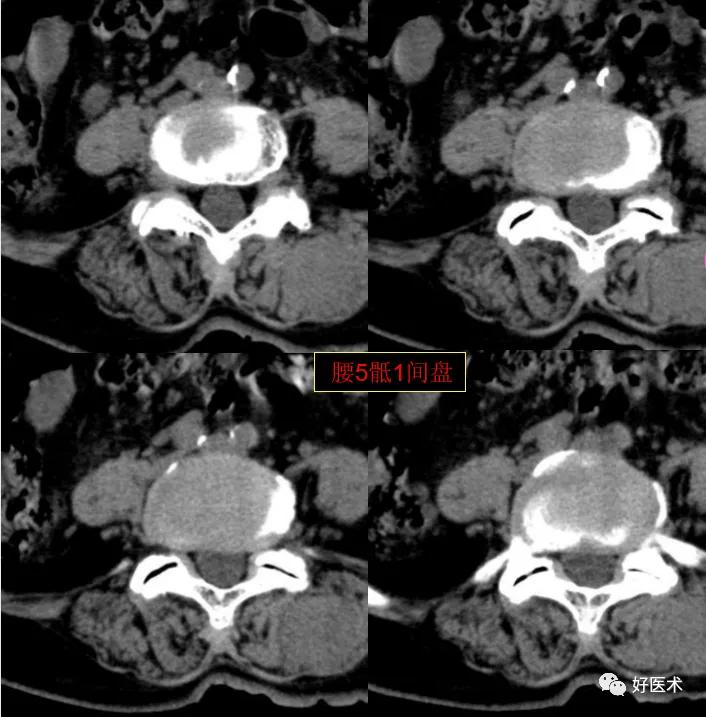

腰5骶1间盘膨隆,双侧椎小关节积气

发现了什么?左侧竖脊肌较右侧明显肿胀饱满, 肌间脂肪间隙消失!!

终于知道了是什么鬼在作乱, 找到了左侧竖脊肌肿胀的元凶:肺癌转移。